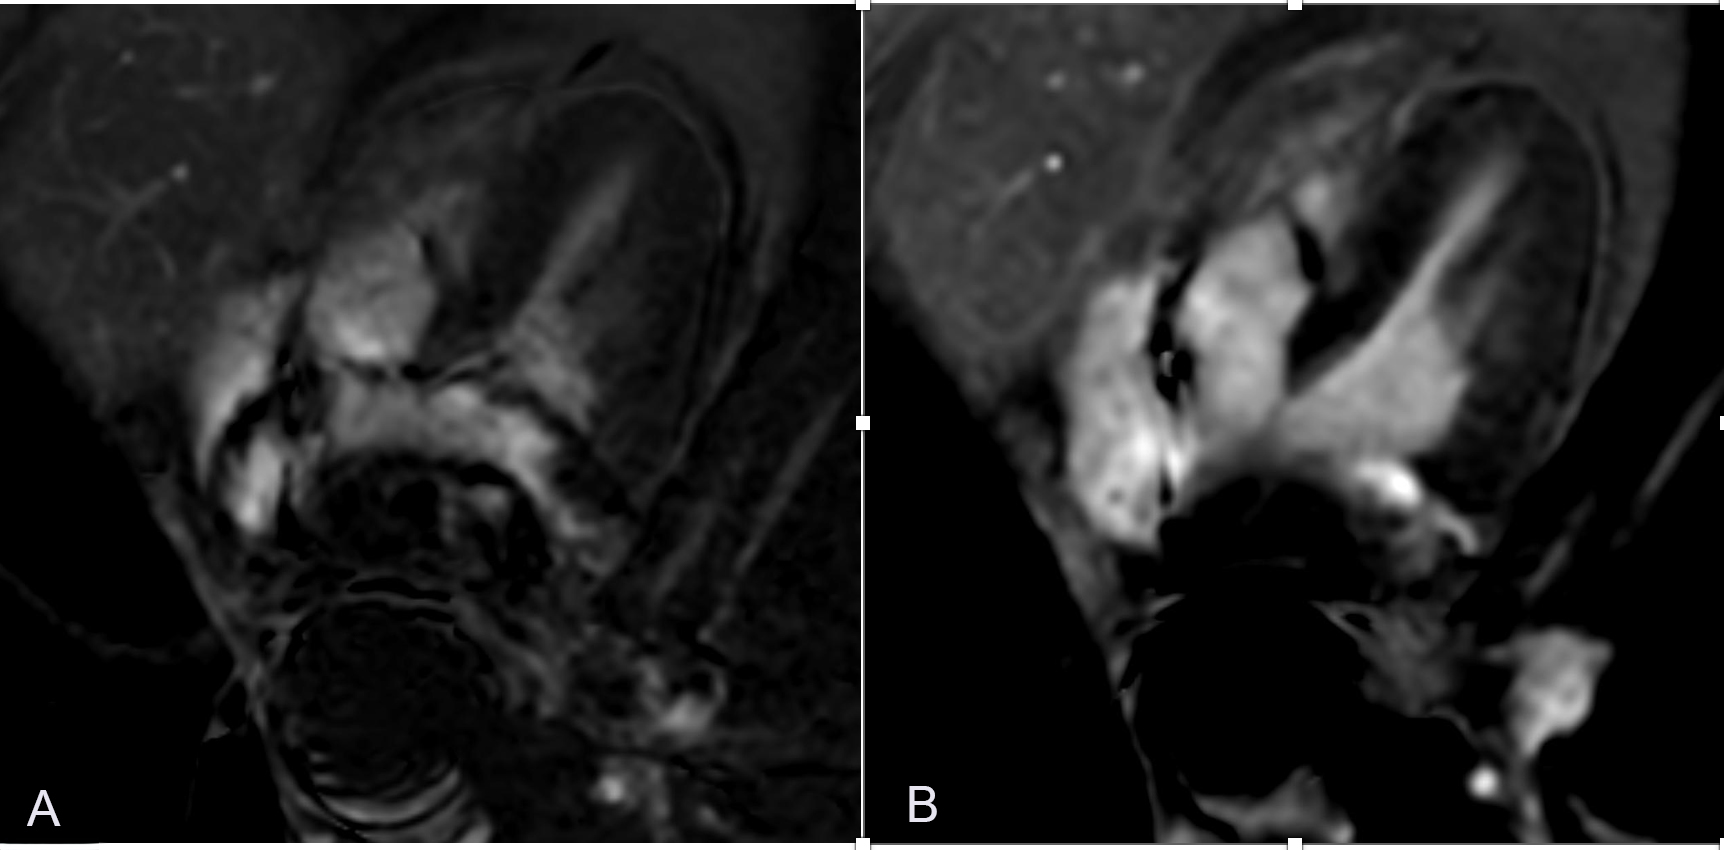

Figure 2. 63-year-old male patient with a pacemaker and LINX device in the gastroesophageal junction. (A) SSFP-based single-shot phase-sensitive LGE demonstrating severe degradation of diagnostic confidence secondary to the metal artifact. (B) SPGR-based single-shot phase-sensitive LGE demonstrating significantly improved diagnostic confidence with visualization of the entire left ventricular myocardium.